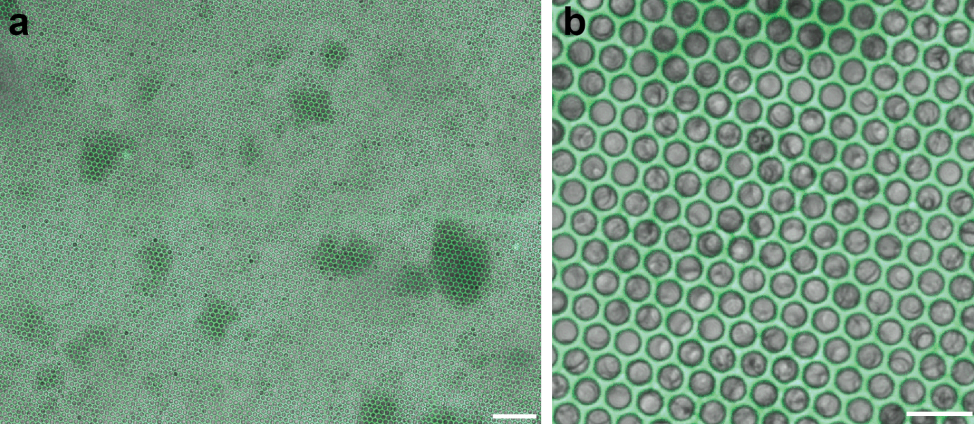

科学公司的设备并没有将任何东西植入大脑,而是放在大脑上面。但这种设备并不仅仅是一块贴在大脑表面的板子——它充满了神经元。神经元位于一个类似华夫饼的装置的孔中,然后附着在大脑表面,神经元朝下。神经元向下生长进入大脑,充当设备和大脑组织之间的粘合剂。

该装置看起来像一个华夫饼,上面有一个个被称为微孔的小碟子,每个直径为 10 微米,安装在透明底板上。每个微孔容纳一个神经元,每个装置约5毫米见方,平均容纳9万个神经元。生物混合装置中的神经元长到了大脑皮层的最顶端,血管也长到了新的神经元中。